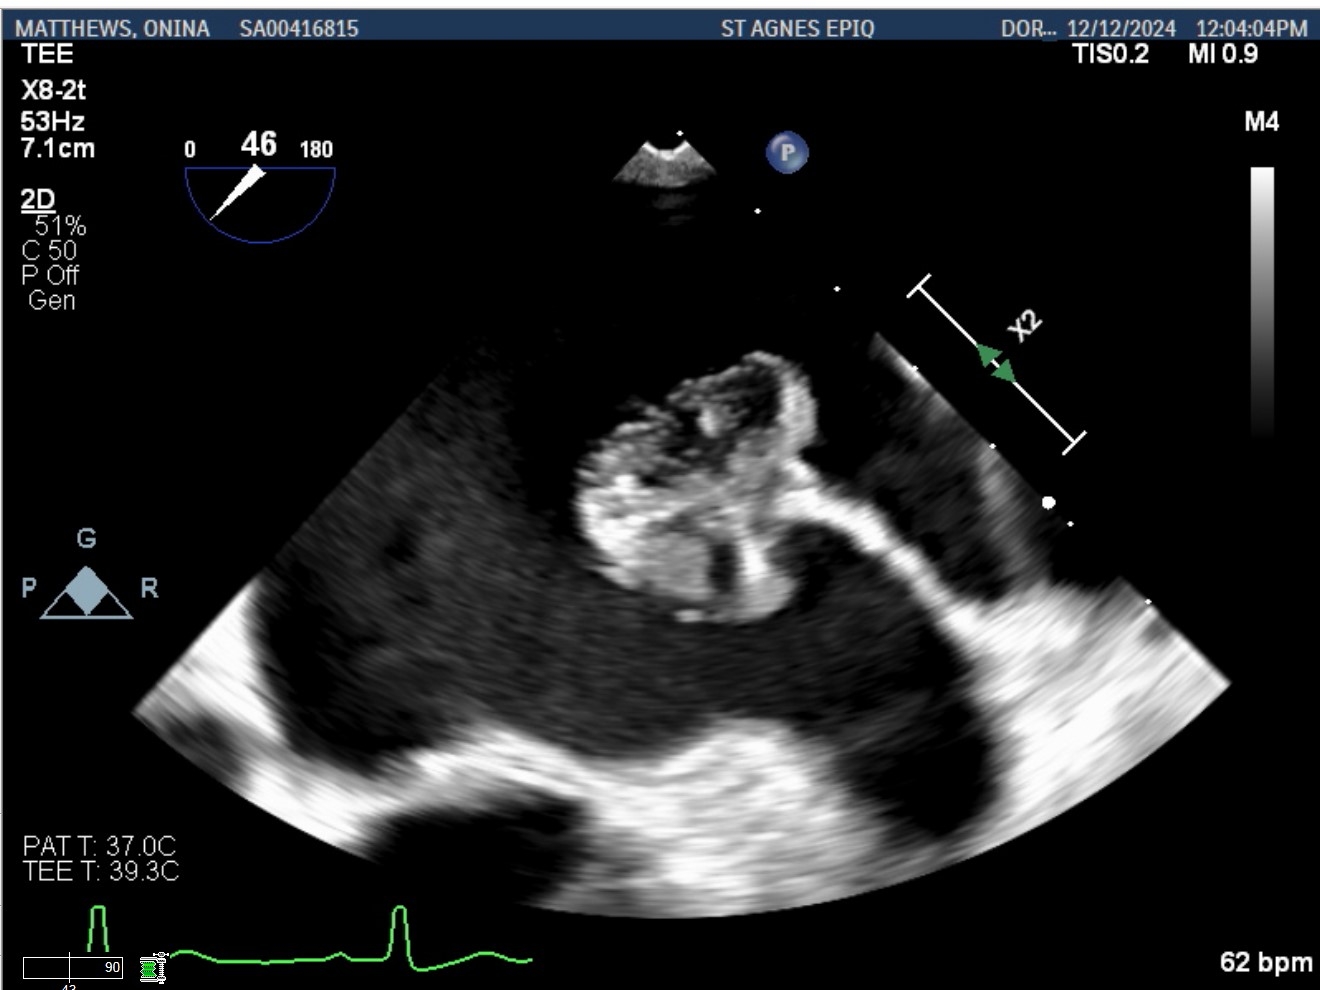

Case Presentation: A 70-year-old woman was evaluated for a TAVR workup due to recent worsening of fatigue and dyspnea. Physical examination revealed grade three ejection systolic murmur with diminished S2 and severe aortic stenosis was noted on transthoracic echocardiogram. Cardiac CT showed an atrial mass. Transesophageal echocardiography demonstrated a heterogenous left atrial mass measuring 2.7 x 2.4 cm; originates from the tip of the Coumadin ridge, independently mobile with a dandelion-like gelatinous appearance, and did not take up Definity contrast (Figures 1, 2, 3). The patient underwent surgical aortic valve replacement with mass excision through the interatrial septum. Pathologic examination revealed 2.5 x 2.2 x 1.5 cm tan-white, villous, gelatinous soft tissue consistent with fiberoelastoma.